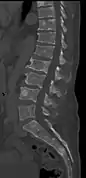

The diagnostic examination of a person with suspected multiple myeloma typically includes a skeletal survey. This is a series of X-rays of the skull, axial skeleton, and proximal long bones. Myeloma activity sometimes appears as "lytic lesions" (with local disappearance of normal bone due to resorption) or as "punched-out lesions" on the skull X-ray ("raindrop skull"). Lesions may also be sclerotic, which is seen as radiodense.[70] Overall, the radiodensity of myeloma is between −30 and 120 Hounsfield units (HU).[71] Magnetic resonance imaging is more sensitive than simple X-rays in the detection of lytic lesions, and may supersede a skeletal survey, especially when vertebral disease is suspected. Occasionally, a CT scan is performed to measure the size of soft-tissue plasmacytomas. Nuclear Medicine Bone scans are typically not of any additional value in the workup of people with myeloma (no new bone formation; lytic lesions not well visualized on nuclear bone scan).

CT scan of the lower vertebral column in a man with multiple myeloma, showing multiple osteoblastic lesions: These are more radiodense (brighter in this image) than the surrounding cancellous bone, in contrast to osteolytic lesions, which are less radiodense.